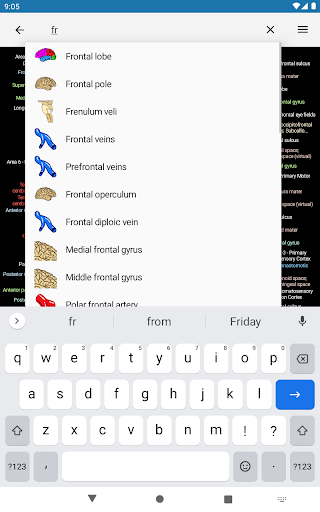

- Localice fácilmente las estructuras anatómicas gracias a la búsqueda de índice

*Encuentre sus partes anatómicas más fácilmente gracias a la nueva función de búsqueda, más intuitiva y poderosa.

Ahora podrás ver tus búsquedas más recientes.